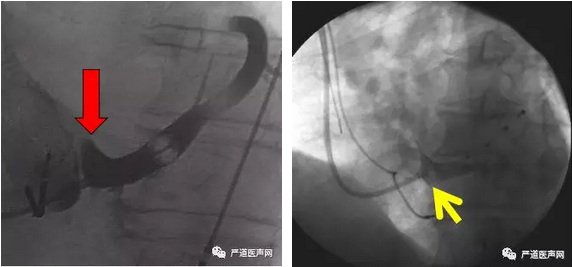

冠状窦口存在瓣膜(Thebesian瓣)

55/75 hearts:73%

CS开口处的Thebesian 瓣

冠状窦口存在瓣膜术中可能的征象:

● 1.导线、EP电极及PTCA钢丝等入CS,但指引导管不能进入;

● 2.通过指引导管在房内造影,可见窦口常成平面,似“刀削状”影像。